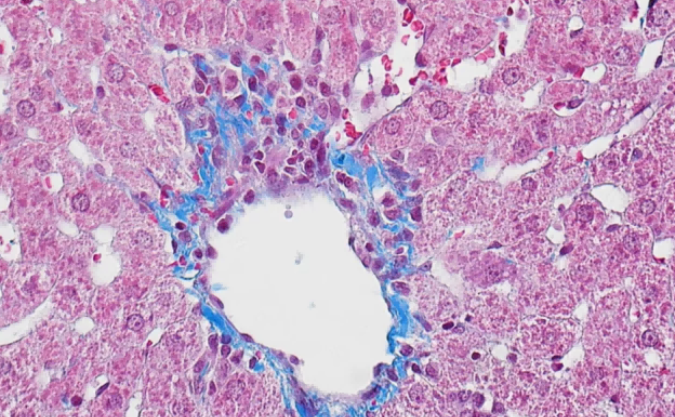

真菌荧光检测系统MS60,改变了临床这一难题,实现了类似从“传统手动对焦相机到傻瓜相机”模式的转变,提供了检查效率,缩短了患者等候时间,提供了皮肤病的诊断准确率

明美显微镜相机MS60采用高性能的成像芯片,设计USB3.0数据传输接口,具有高帧率、颜色还原准确的特点。图像清晰、色彩表现丰富,是病理诊断的理想工具。同时也是金相分析和体视观察等应用领域的理想工具。